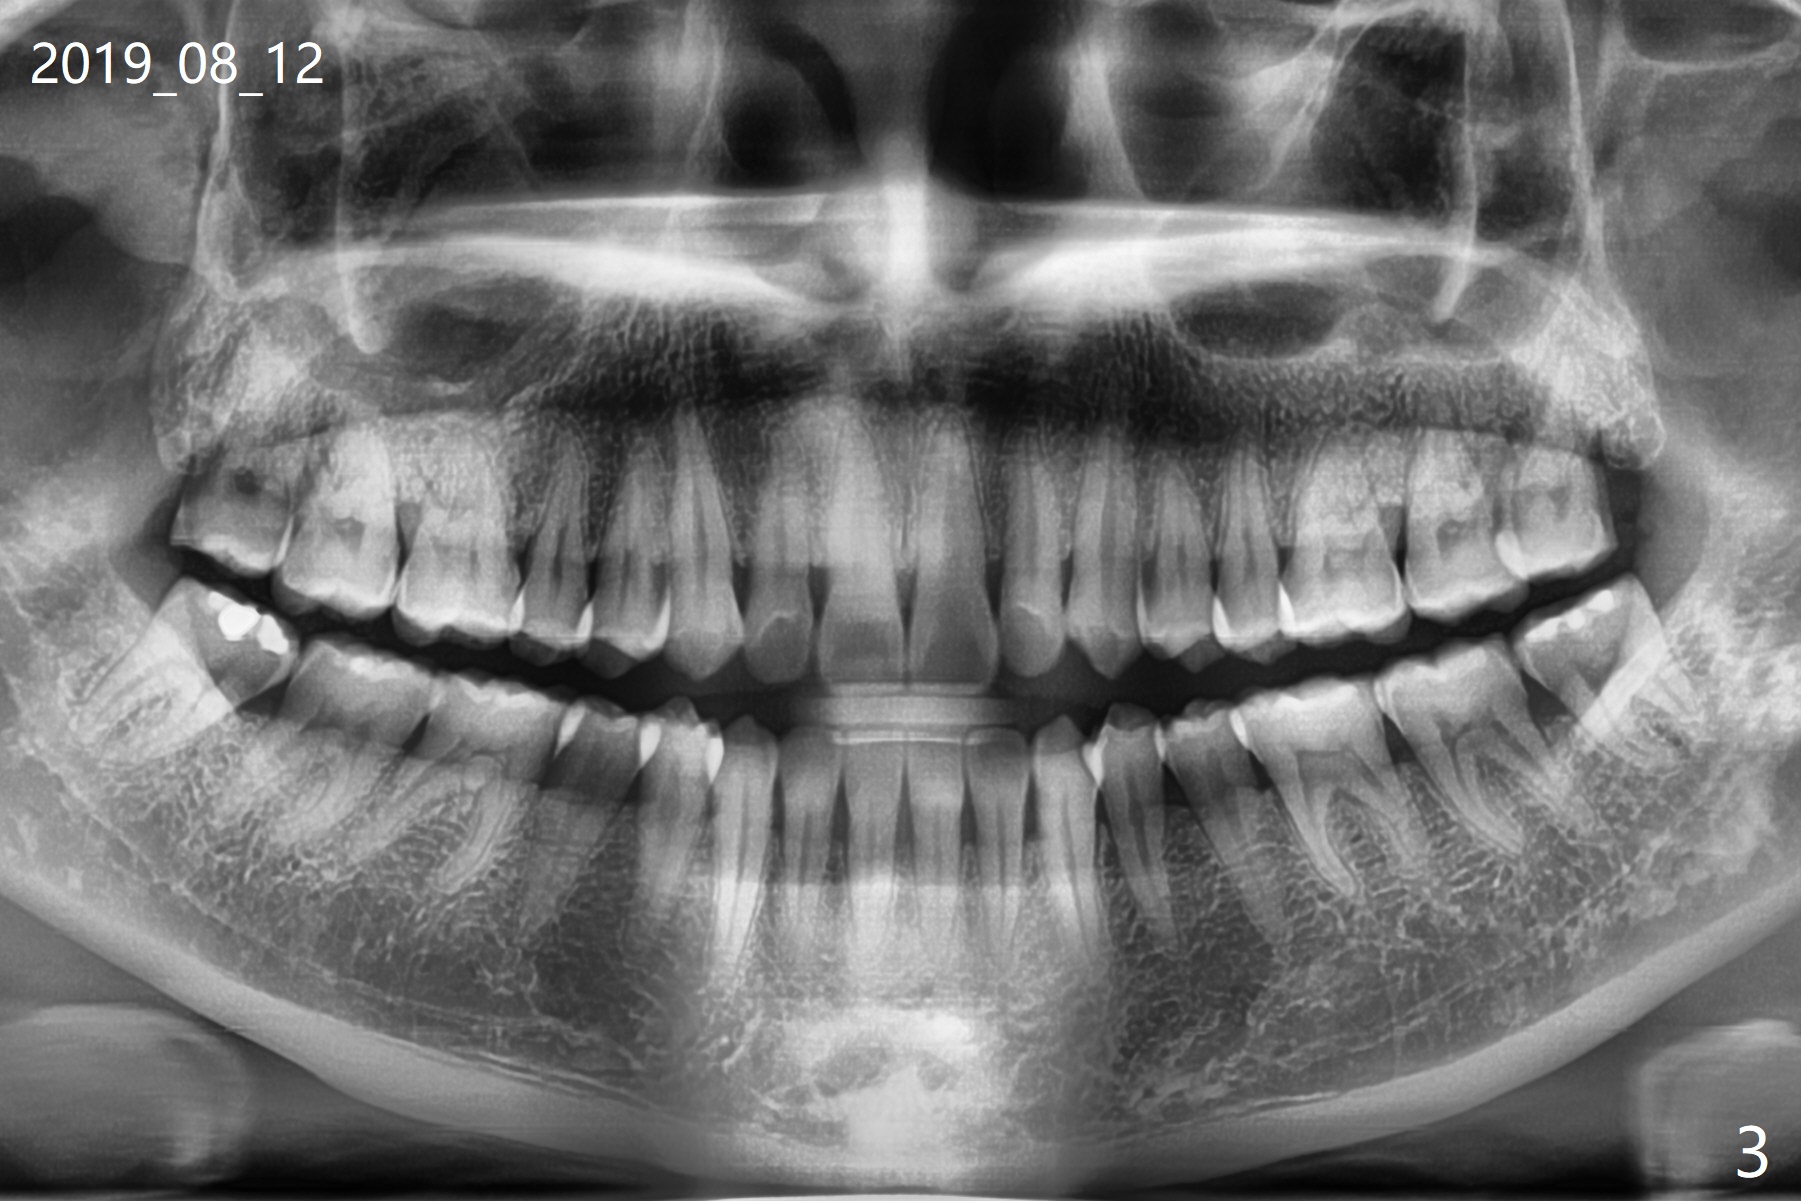

A 35-year-old woman requests extraction of the tooth #1 (food impaction between #1 and 2, Fig.1) and 16 (pain and 6 mm pockets between #15 and 16, Fig.2). In spite of the fact that there is bone loss between #14 and 15 (Fig.3), there is no deep pocket between them. After extraction of #16, SRP is performed in the distal surface of #15 with removal of granulation tissue and application of Endogain. Osteogen plug (Fig.4 O) is placed in the apical and distal portion of the socket of #16 (red dashed line), while allograft (G) against the distal root surface of #15. Finally Collagen plug (C) and 6-month membrane are placed in the opening of the socket, followed by suturing and periodontal dressing. The bone density is high post #1 extraction (Fig.6), related to difficult removal. It appears that bone graft at #16 (^) remains in place 15 months postop. Since no buccal trough is made for extraction, the external oblique ridge is present at #17 and 32 before and after surgery. Bond Apatite is placed with Collagen Plug (Fig.7).